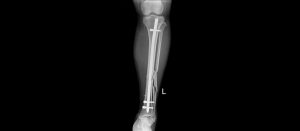

Hình ảnh chụp X-quang xương cẳng chân của bệnh nhân trước và sau phẫu thuật

Sau 1 giờ phẫu thuật dưới hướng dẫn của hệ thống C-arm, kết quả kiểm tra phim chụp X-quang 2 xương cẳng chân của bệnh nhân cho thấy xương nắn chỉnh tốt. Sau mổ 1 ngày bệnh nhân đã giảm đau rõ rệt và đã có thể tập vận động. Sau phẫu thuật 7 ngày, tình hình sức khỏe của bệnh nhân hồi phục tốt và đã được ra viện vào ngày 02/10/2023.

BSCKI. Đào Văn Quang, Phó Trưởng khoa Chỉnh hình – Bỏng Bệnh viện Đa khoa tỉnh Thanh Hóa cho biết: “Đối với những trường hợp chấn thương như bệnh nhân T., việc sử dụng phương pháp phẫu thuật kết hợp xương bằng đinh nội tuỷ có chốt đóng kín dưới hướng dẫn của hệ thống C-arm là phương pháp tối ưu nhất. So với phương pháp mổ mở thông thường thì phương pháp nắn kín kết hợp xương trên C-arm này có nhiều ưu điểm hơn như: Hệ thống C-arm giúp cho các phẫu thuật viên định hướng đặt các đinh ốc vít vào xương được chính xác hơn và không cần phải mổ rộng chỗ cần can thiệp ra, hạn chế nhiễm trùng vì vẫn giữ được ổ gãy kín, hoặc chỉ mở tối thiểu. Bảo toàn được cấu trúc giải phẫu, nhất là mạch máu thần kinh và gân cơ, đảm bảo được hoàn hảo về chức năng chi thể và tính thẩm mỹ. Bệnh nhân ít đau đớn hơn. Chi phí điều trị thấp hơn, bởi thời gian nằm viện chăm sóc ngắn hơn, thuốc dùng ít hơn…”.